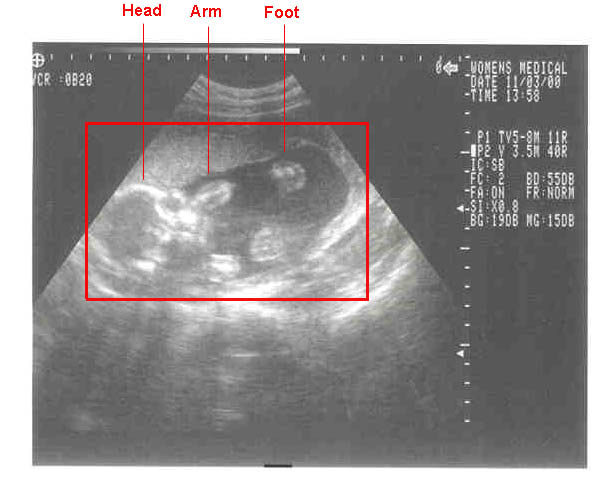

11/03/2000--Head-on shots at 20 weeks. Weight approx. 1 pound.